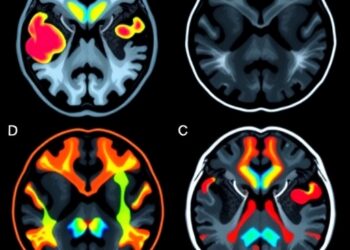

The team’s goal was to understand how low-frequency brain oscillations in the theta (4-8 Hz) to alpha (8-12 Hz) range, which have been found by a large body of scientific literature to play a prominent role in cognitive processes, were altered in individuals with severe, treatment-resistant OCD. To do so, they took advantage of a novel feature of modern DBS devices – the ability to not only deliver stimulation but also record brain activity.

Recordings started upon implantation of the DBS system. Because stimulation is typically initiated days to weeks later, the team was able to measure neural activity patterns in the severely symptomatic state. Interestingly, they found that 9 Hz (theta-alpha border) ventral striatum neural activity demonstrated a prominent circadian rhythm that fluctuated over the 24-hour cycle.

“Before DBS, we saw an extremely predictable and periodic neural activity pattern in all participants,” said Dr. Goodman, professor and D. C. and Irene Ellwood Chair in Psychiatry in the Menninger Department of Psychiatry and Behavioral Sciences at Baylor College of Medicine. “However, after DBS activation, as individuals began responding and improving symptomatically, we saw a breakdown in this predictable pattern. This is a very interesting phenomenon and we have a theory to explain it. Individuals with OCD have a limited repertoire of responses to any given situation. They often perform the same rituals repeatedly and seldom vary their routines or engage in new activities, which may result in high predictability of activity in this brain region. However, after DBS activation, their behavioral repertoire is expanded; they might respond more flexibly to situations and not be just driven by a strong desire to avoid OCD triggers. This expanded repertoire may be a reflection of the more diverse brain activity pattern. Thus, we think this loss of a highly predictable neural activity indicates that the participants engaged in fewer repetitive and compulsive OCD behaviors.”